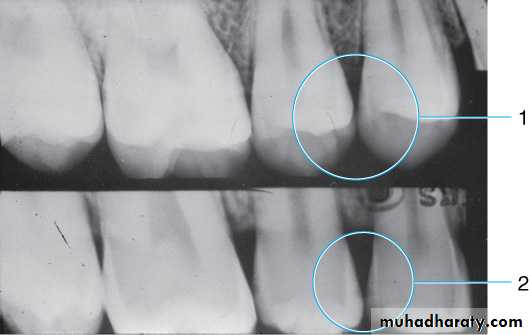

Vertical angulation

(A) Improper vertical angulation (excessive) obliterates viewing this proximal surface carious lesion. (B) Proper vertical angulation shows interproximal cariesDental Caries